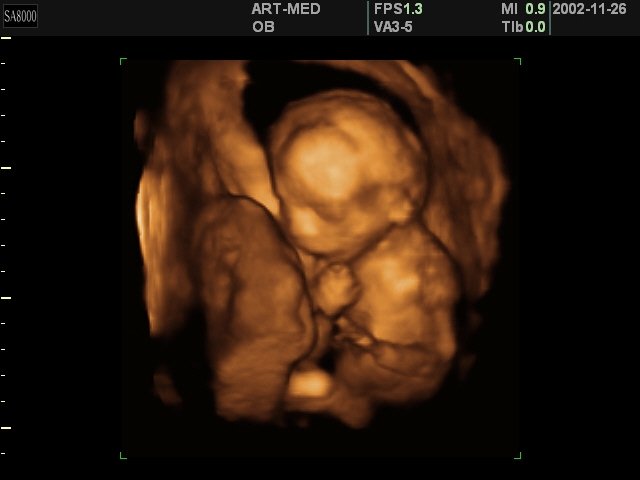

С помощью трехмерного УЗИ будущая мама может увидеть изображение своего ребенка, близкое к фотографии, и получить видеозапись его движений в реальном времени.

Что же увидит будущая мама на мониторе прибора в ходе такого исследования? Трехмерное УЗИ позволяет получить объемное изображение эмбриона на таком маленьком сроке беременности, когда его длина составляет всего 15 мм.

К 12-ой неделе можно увидеть уже сформировавшееся тело плода: голову, туловище, руки, ноги, глаза, нос, рот, уши. На экране виден плод целиком, причем рассмотреть его можно со всех сторон.

В 20 недель возможно уже различить каждый пальчик. К 5 месяцам плод заметно вырос, он двигается, совершая координированные движения, принимает различные позы, сосет пальчик, закрывает лицо руками.

К 28 неделе у плода округляются щечки, лицо становится более сформированным, различимы губы, нос. Он может почесать ухо, сложить кулачки, зевнуть, состроить гримасу, улыбнуться. И это все будущая мама видит на экране в реальном времени.

Благодаря трехмерному ультразвуку врачи могут оценить различные части тела плода в трех проекциях одновременно, что очень важно для выявления пороков развития. Кроме того, данная методика помогает в определении пола ребенка, когда визуализация области промежности затруднена положением плода в полости матки.